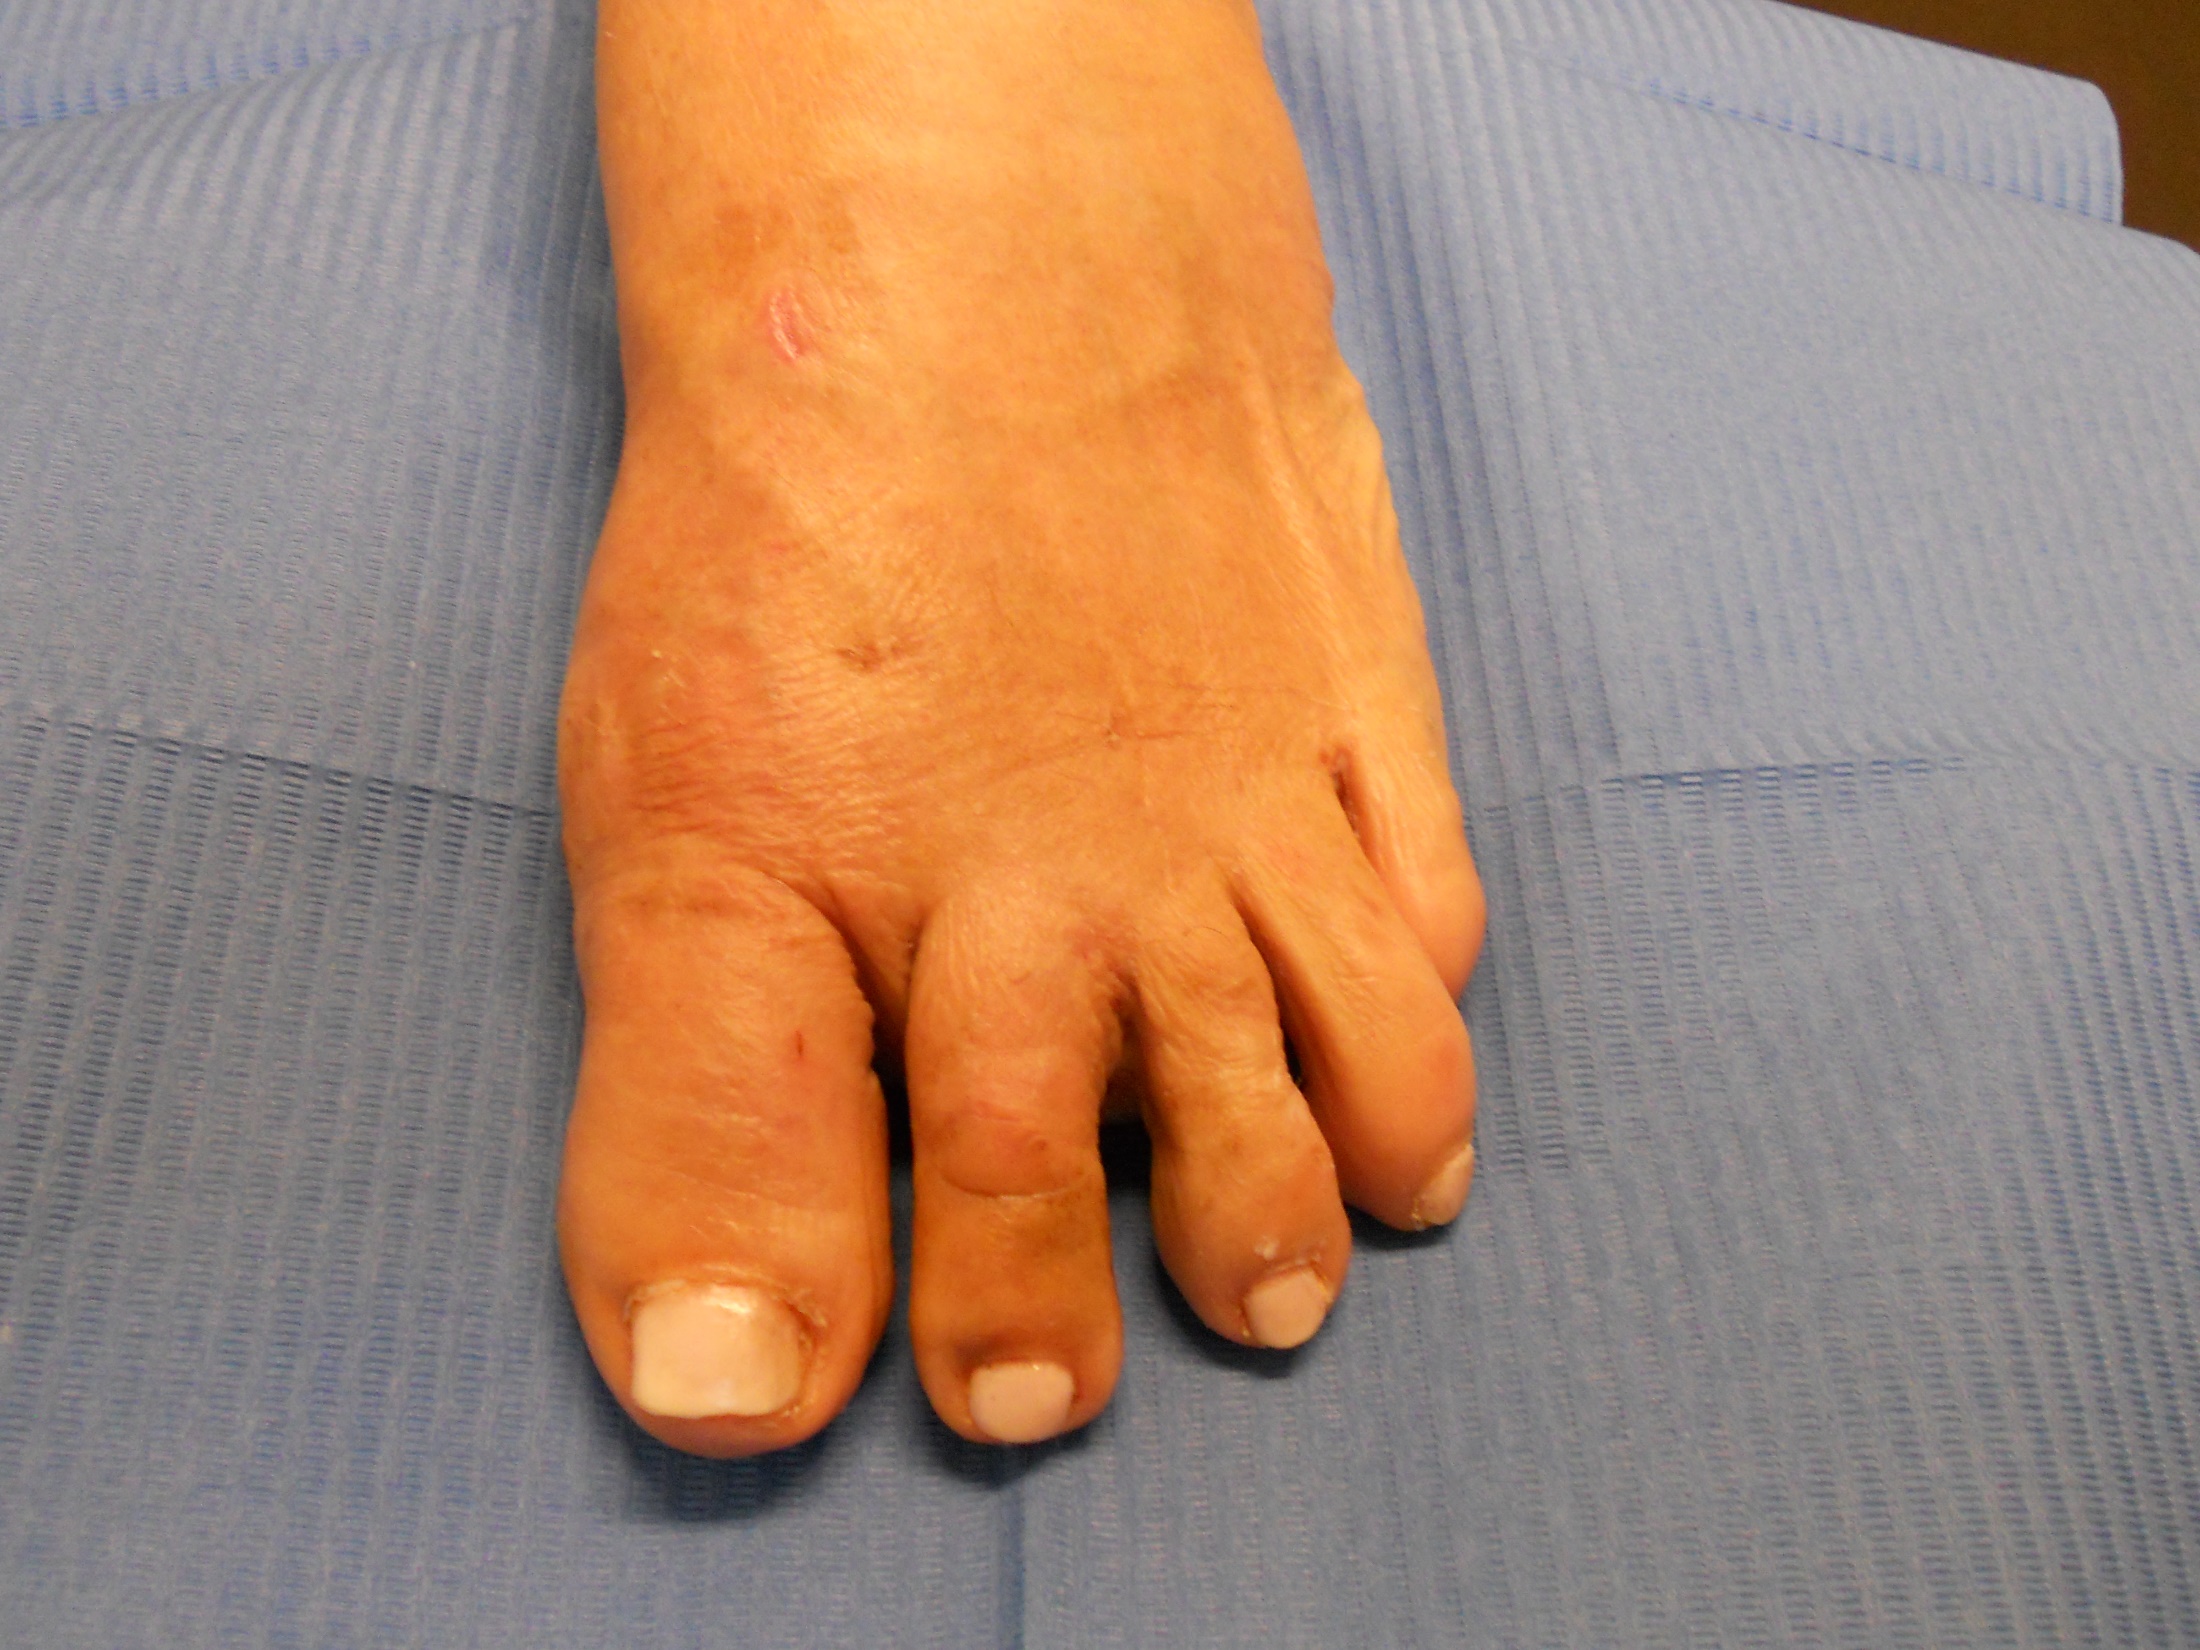

Hallux valgus (juanete) y dedos en garra

Hallux valgus (juanete) y dedos en garra: antes Hallux valgus (juanete) y dedos en garra: después

Hallux Valgus (juanete)

Hallux valgus: antes Hallux valgus: después